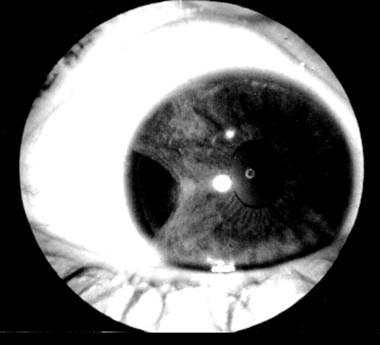

Iridodializa

PLANSA VI - TRAUMATISME OCULARE

dezinsertii la nivelul radacinii irisului (iridodializa-vezi plansa),

Iridodializa si recesia unghiului camerular se asociaza de regula de cresterea tonusului ocular.